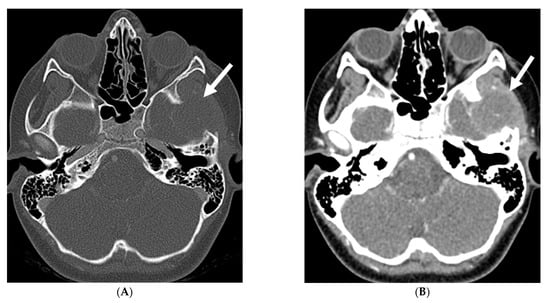

Fungal infections of the central nervous system (CNS) can be broadly categorized into two forms based on the causative organism’s size and pathogenesis. Yeast infections (e.g., Cryptococcus, Candida) are smaller and disseminate hematogenously, resulting in parenchymal granulomas, abscesses, and diffuse leptomeningitis. Mold infections (e.g., Aspergillus, Mucorales) are larger fungi that are restricted from entering the meningeal microcirculation, leading to more focal disease manifestations such as cerebritis, abscess formation, vasculitis, infarct, and mycotic aneurysm [99]. Candida is the most common fungal organism affecting children, typically in preterm and/or low birth weight neonates [100]. The routes of CNS invasion by fungal pathogens include hematogenous dissemination from a distant source (commonly lung), direct inoculation following trauma or neurosurgical procedures, and local extension from adjacent structures like the paranasal sinuses, orbit, or spine [101].

MRI findings in fungal meningitis include LME, which can be smooth or thick, nodular and irregular, and commonly involve the cortical sulci [102]. While a smooth, linear enhancement pattern is common in viral and bacterial meningitis, it can also be seen in immunocompetent patients with fungal meningitis [102]. Inflammatory exudates containing cell debris, fibrin, and hemorrhage can deposit in the subarachnoid space, leading to arachnoiditis. Protein accumulation in the subarachnoid space shortens T1 relaxation time and results in increased signal intensity on FLAIR sequences [102]. Meningeal adhesions can obstruct arachnoid granulations, leading to impaired cerebrospinal fluid (CSF) drainage and secondary hydrocephalus. Fungal brain abscesses typically demonstrate a central T1 hypointense and T2 hyperintense core, surrounded by a T1 iso-to-hyperintense and T2 hypointense enhancing peripheral rim (Figure 20) [103,104].

Figure 20.

Axial T2 (A), axial DWI (B), axial SWI (C) and axial T1 post contrast (D): 4-year-old girl with acute lymphoblastic leukemia, pancytopenia and fever. Treatment started one week before with asparaginase. There is prominently T2 hyperintensity and swelling of the gyri involving the medial aspect of the left parietal occipital cortex (arrow). Multiple small foci of T2 hypointensities are identified within the involved region with corresponding blooming on the susceptibility indicating hemorrhage (curved arrow) and peripheral rim of true restricted diffusion (dashed arrow). Postcontrast images show pachymeningeal and LME in the involved region (open arrows). Features are concerning for fungal infection. Pathology revealed Rhizomucor pusillis (thermophilic fungus).